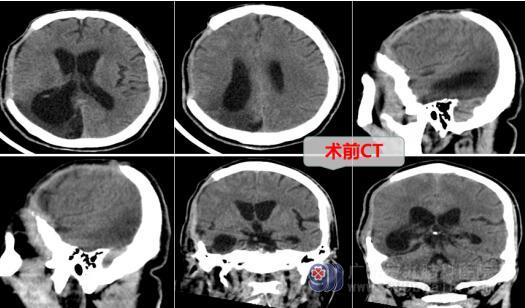

来自广东茂名的蔡先生(化名)今年57岁,三个月前的一天发生了车祸,这次事故损伤到他的头部,当时情况紧急,家属将他送到当地医院就医,头颅CT显示右侧额颞顶部急性硬膜下血肿,急诊进行了血肿清除术和去骨瓣减压术,得以保住他了生命。

蔡先生家属联系了广东三九脑科医院外十科,欧阳辉主任及其团队对蔡先生制定了手术方案,主管医生向家属讲解手术方式并取得同意。手术当日在全麻下进行了右侧额颞顶颅骨修补术,手术过程顺利,术后切口愈合良好,蔡先生的头颅又恢复了以前的完整性,外形对称、美观。